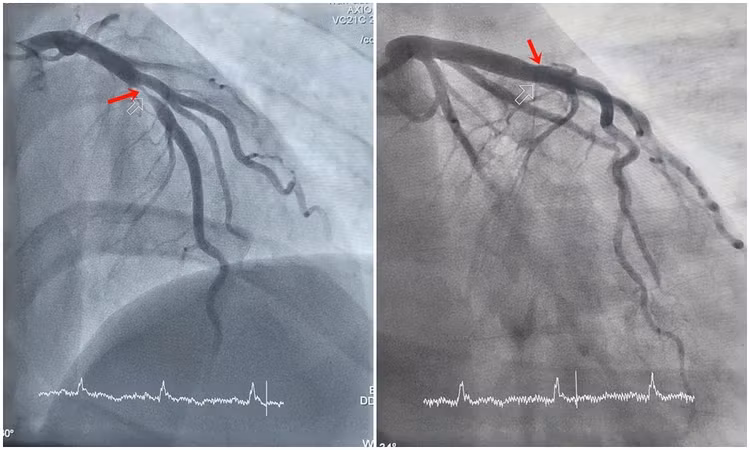

Bệnh nhân nhanh chóng được chuyển phòng can thiệp chụp mạch vành kiểm tra. Kết quả chụp cho thấy động mạch liên thất trước - một trong những nhánh mạch vành quan trọng nuôi dưỡng cơ tim, bị tổn thương nặng, hẹp khít 99%. Trước tình trạng nguy hiểm, các bác sĩ khoa Phẫu thuật và Can thiệp Tim mạch thực hiện can thiệp đặt stent nhằm tái thông máu nuôi tim, giúp người bệnh thoát khỏi tình trạng nguy hiểm.

Hình ảnh hẹp tắc động mạch liên thất trước của bệnh nhân H. được can thiệp tái thông. Ảnh BV